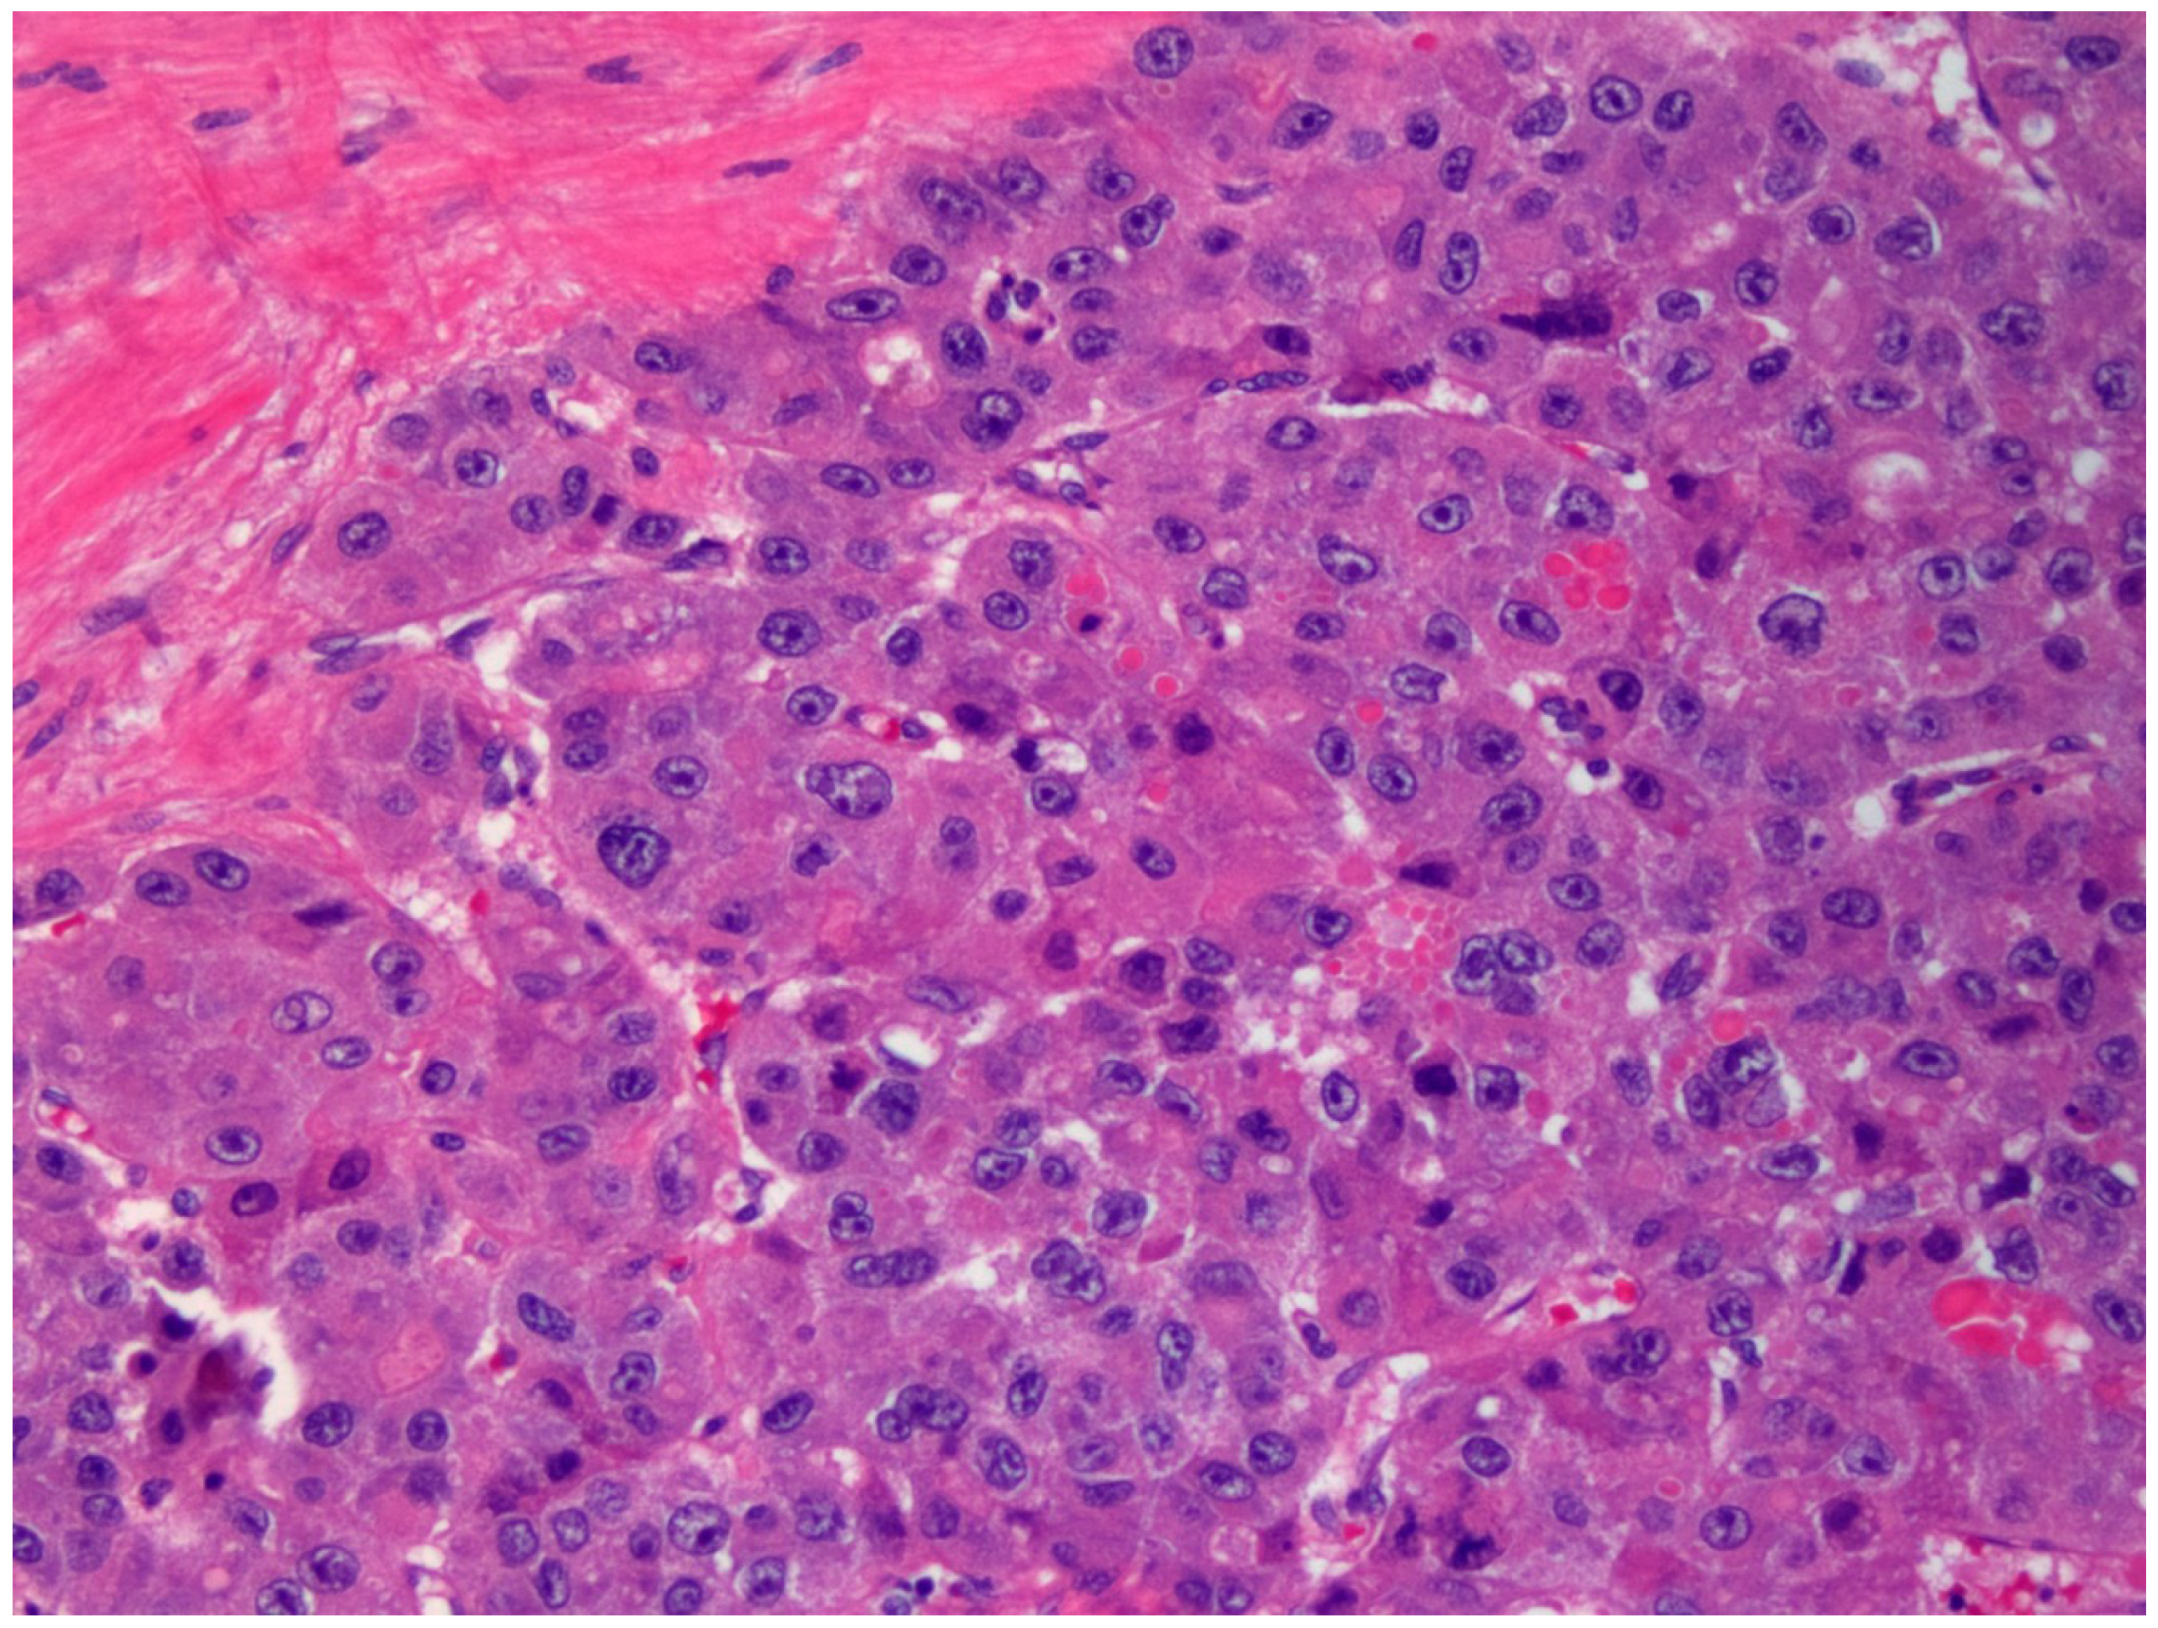

2. Gross Anatomy and Microscopy